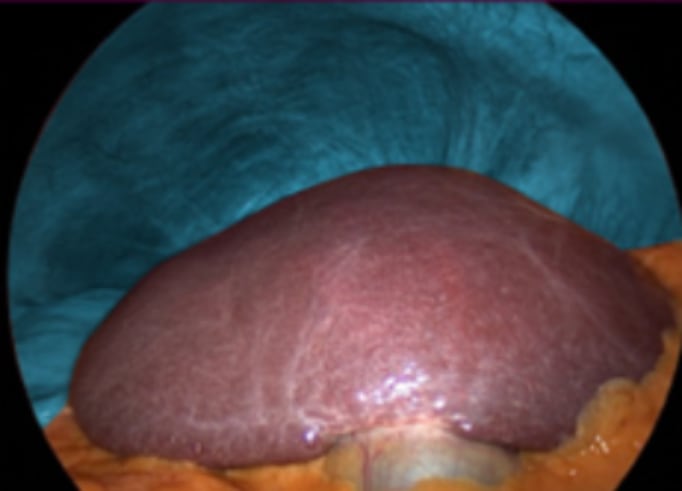

1. Other organs such as the transverse colon, stomach, and small intestine fall to the lower left while the liver stays in place (coronary /triangular ligaments). This is a big advantage for nonanatomical resections in segment 8 where mobilization of the liver is often unnecessary

Nonanatomical resection for colorectal liver metastasis in segment 8. Without mobilizing the right hemiliver a good view is obtained.